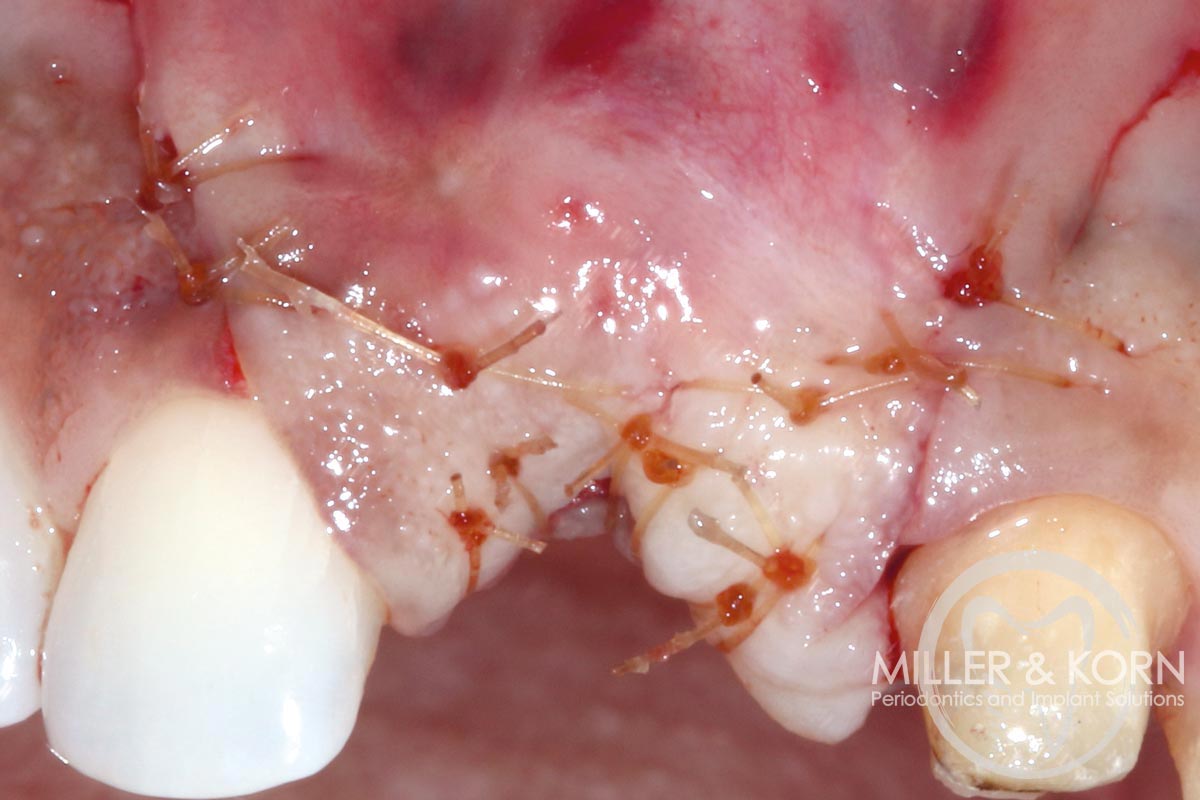

15/22 - Closing the flap.Immediate implant placement and regeneration of ridge using an allograft bone ring and Jason® membrane - Drs. Miller and Korn